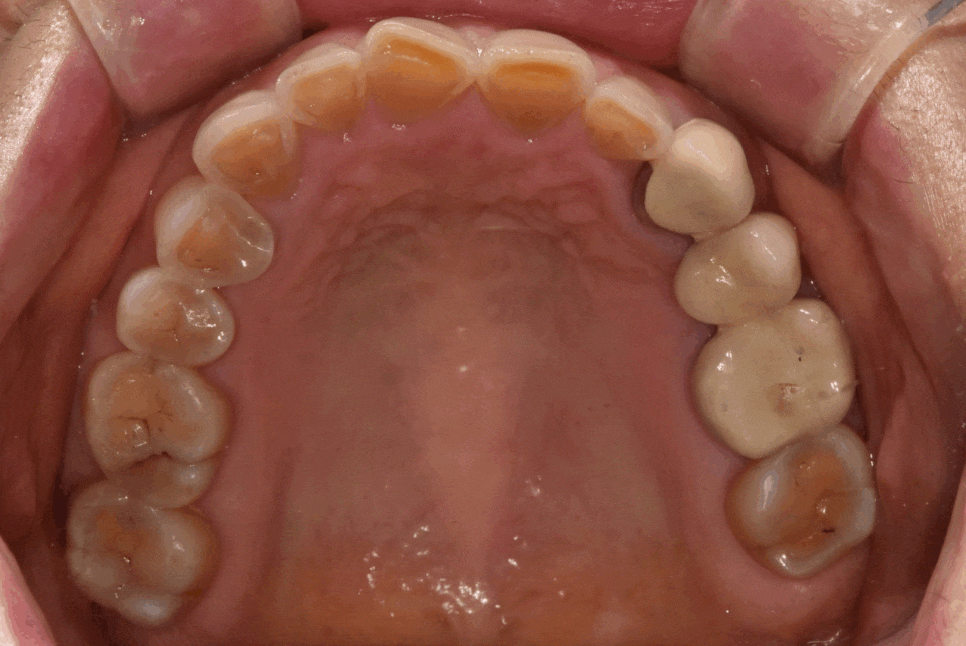

실제로 보니 치경부 쪽(치아와 잇몸 경계)이

전체적으로 어두웠습니다.

하지만 그보다 더 큰 문제는

전체적으로 씹는 면이 많이 닳아있다는 점인데요,

이건 씹는 힘이 남들보다 강하다는 증거입니다.

이런 분이 라미네이트를 하면 어떻게 될까요?

깨지거나 떨어질 확률이 매우 높습니다.

그래서 라미네이트보다 강도가 더 높은

지르코니아 크라운을 추천드렸습니다.